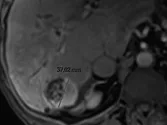

Figure 1. Patient porteur de métastases hépatiques de cancer colique.

Sur l’examen initial (A, B), il existe de multiples lésions secondaires.

Deux cibles sont choisies dans le foie droit, une à hauteur de la bifurcation portale (A) une autre dans le segment VI (B). D’autres lésions mesurables existent, mais seront considérées comme non cible (A). Après six mois de chimiothérapie (C, D), on observe une progression des cibles, des non cibles, et une nouvelle lésion indiscutable dans le segment VI (D)